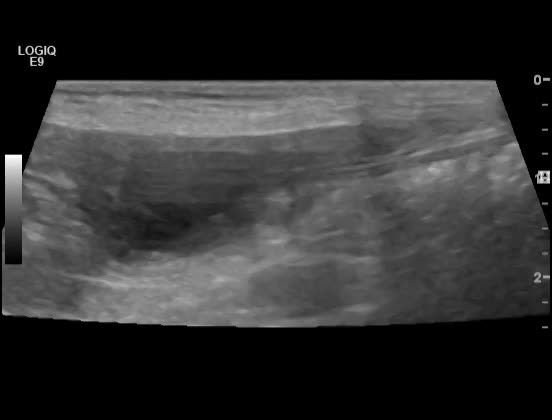

Signalement: Jack Russell terrier, tispe, 13 år Anamnese: Intermitterende hematuri. Tisser inne – selv rett etter lufting